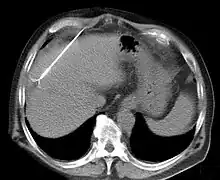

![]() Tissue ablation using radiofrequency. | |